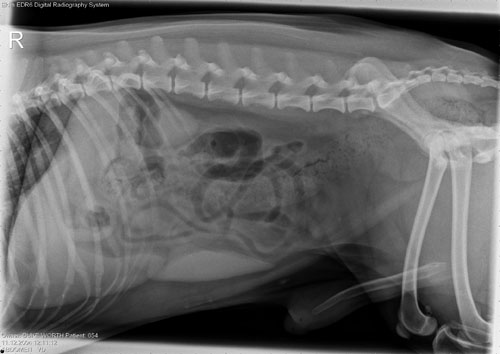

All Creatures Veterinary Clinic uses digital radiography to gather more information about different parts of your pet’s body that we can’t easily see or feel. With digital radiography, we can examine your pet’s internal structures such as bones to diagnose fractures or arthritis. We can check the stomach, intestines, and colon for foreign objects your pet may have swallowed. Chest x-rays are useful for more information about the lungs and heart. We can also look for possible bladder stones.

This technology uses a digital x-ray sensor and electrical impulses to produce the image of the patient’s body on a computer screen. This allows us to view images instantly, enhance and manipulate them for clarity, which all aids in diagnosing complex medical conditions. We can also share the images with a specialist right away if necessary.

The advantages of digital radiography over traditional x-rays includes quicker, enhanced image quality, less radiation exposure for your pets, fewer retakes, cost-effective, quick processing time, and quick sharing.